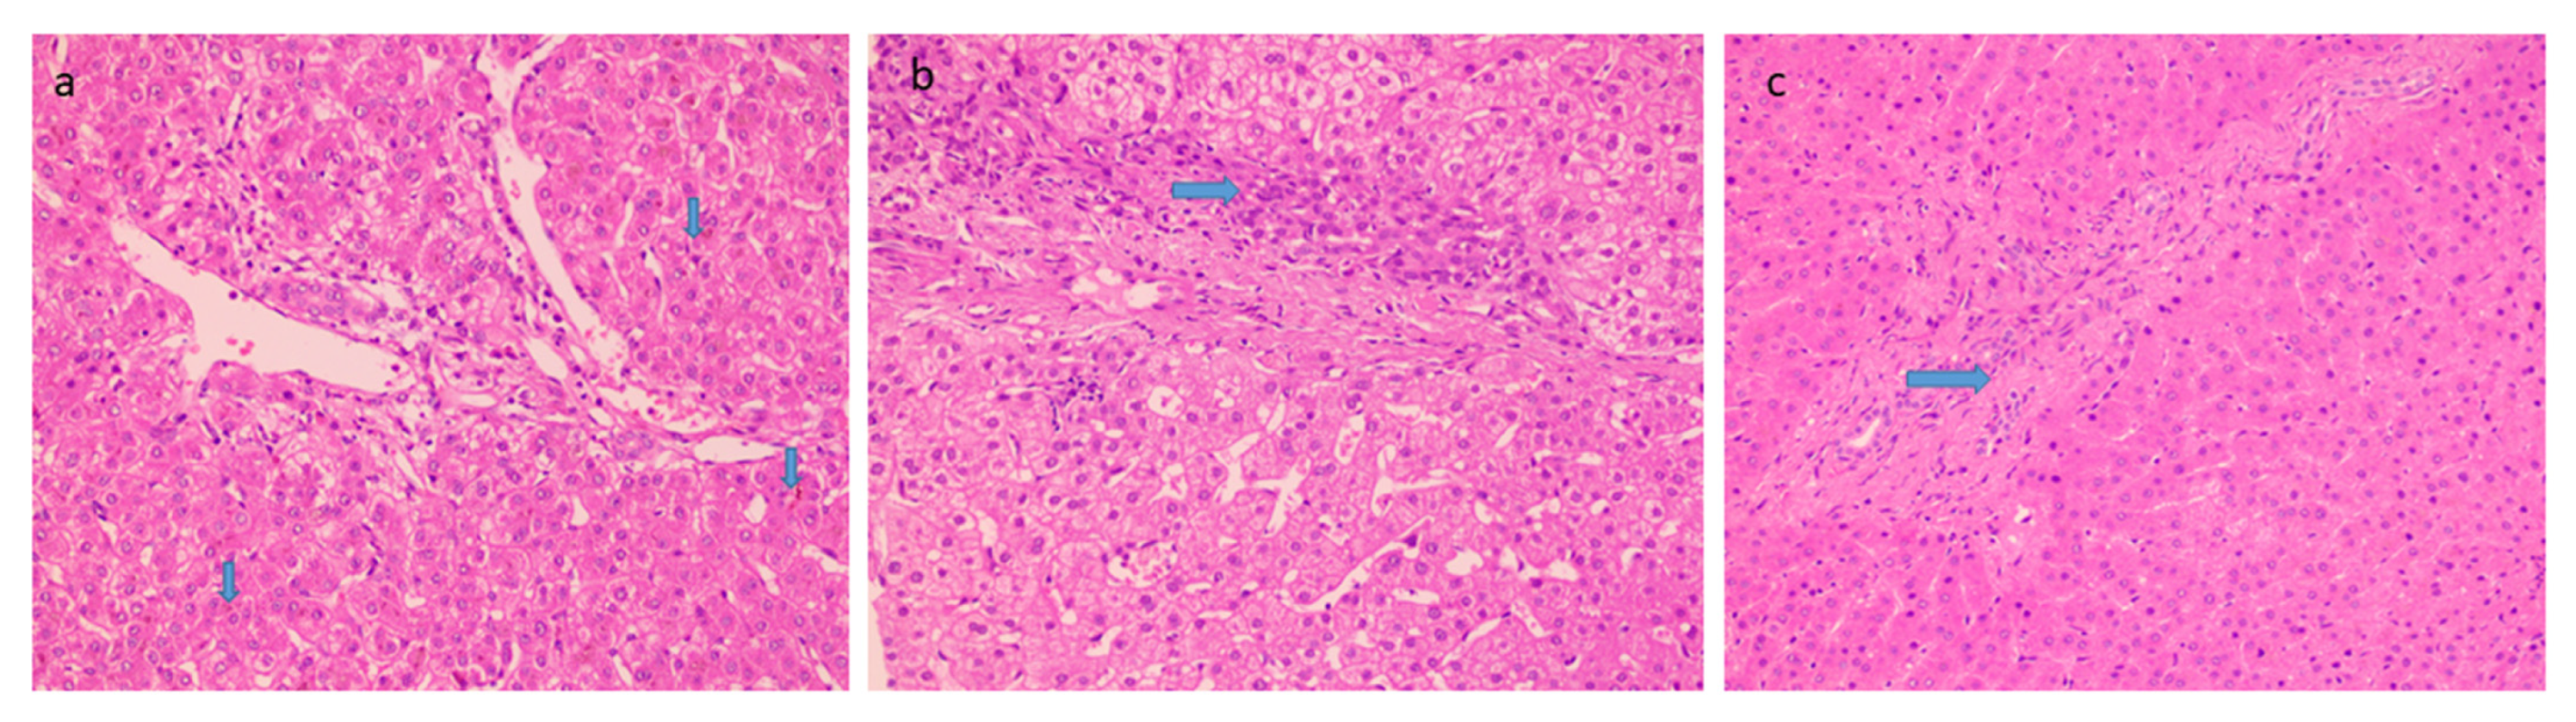

The mean biopsy length was 1.67 ± 0.28 cm with a number of portal tracts of 9.72 ± 3.04. The liver architecture was maintained in the majority of the cases. Histopathological findings in PCC cases are described in Table 3. Portal tracts displayed minimal to mild mononuclear cell inflammation (82%) (Figure 2a). Histological characteristics of EHPVO were noted in the biopsies: portal sclerosis with portal vein phlebosclerosis in 32% (Figure 2b), dilated multiple portal venous channels (72%) (Figure 2c), hepatic artery thickening (70%) (Figure 2d), presence of aberrant vascular channels around portal tracts (54%) (Figure 2e), and elastosis of portal veins (Figure 2f). Remnant portal tracts were found in 20% of the biopsies, and Central vein and sinusoidal dilatation were also recorded in 44% and 26% of the cases respectively.

Figure 2.

Histological characteristics of EHPVO: (a) Minimal Portal Inflammation (20×, HE); (b) portal sclerosis (20×, HE); (c) dilated multiple portal venous channels (20×, HE); (d) hepatic artery thickening (10×, HE); (e) presence of aberrant vascular channels around portal tracts (20×, HE); and (f) elastosis of portal veins (20×, orcein).

Histological features favoring cholangiopathy were found in less than half of the cases and features were of mild grade- bile ductular reaction in 44% (Figure 3a) whereas reactive biliary changes were noted in only 10% of the cases. Hepatocellular and canalicular bile was found in only 9 cases (18%) (Figure 3b). There was increased periportal and/or zone 3 perisinusoidal fibrosis in 38% (Figure 3c). 12% of patients showed the presence of occasional thin fibrous bridges. Cirrhosis or advanced fibrosis was not seen in any of these cases. One-fourth of the cases (12) showed concomitant minimal to mild hepatocyte steatosis.

Figure 3.

Histological features favoring biliopathy (a) bile stasis (20×, HE, arrow) (b) ductular reaction (20×, HE, arrow) and (c) increased periportal fibrosis (20×, HE, arrow).